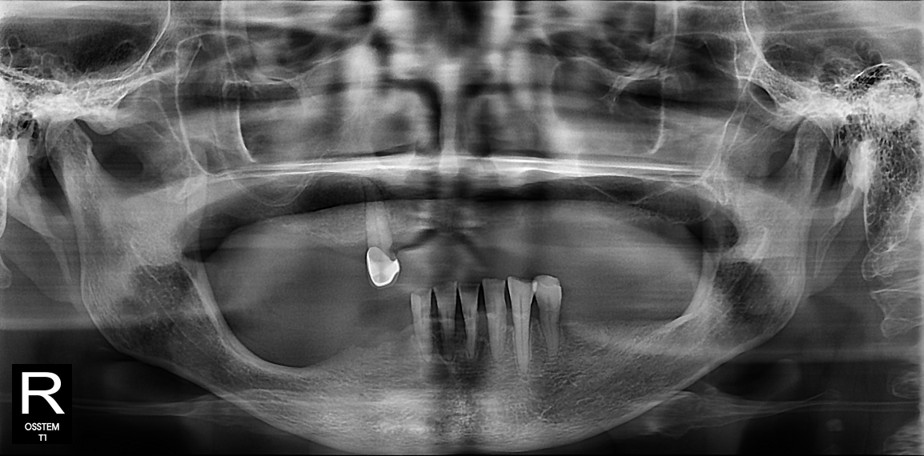

위·아래 모두 틀니를 사용하시던 이번 환자분은 특히 아래쪽 틀니의 들뜸과 통증을 호소하셨습니다.

이번 사례에서는 '올온식스' 공법을 적용했습니다.

이번 환자분도 어금니 쪽 뼈가 부족하고 신경선이 가까워 일반적인 수직 식립이 어려운 상태였습니다.